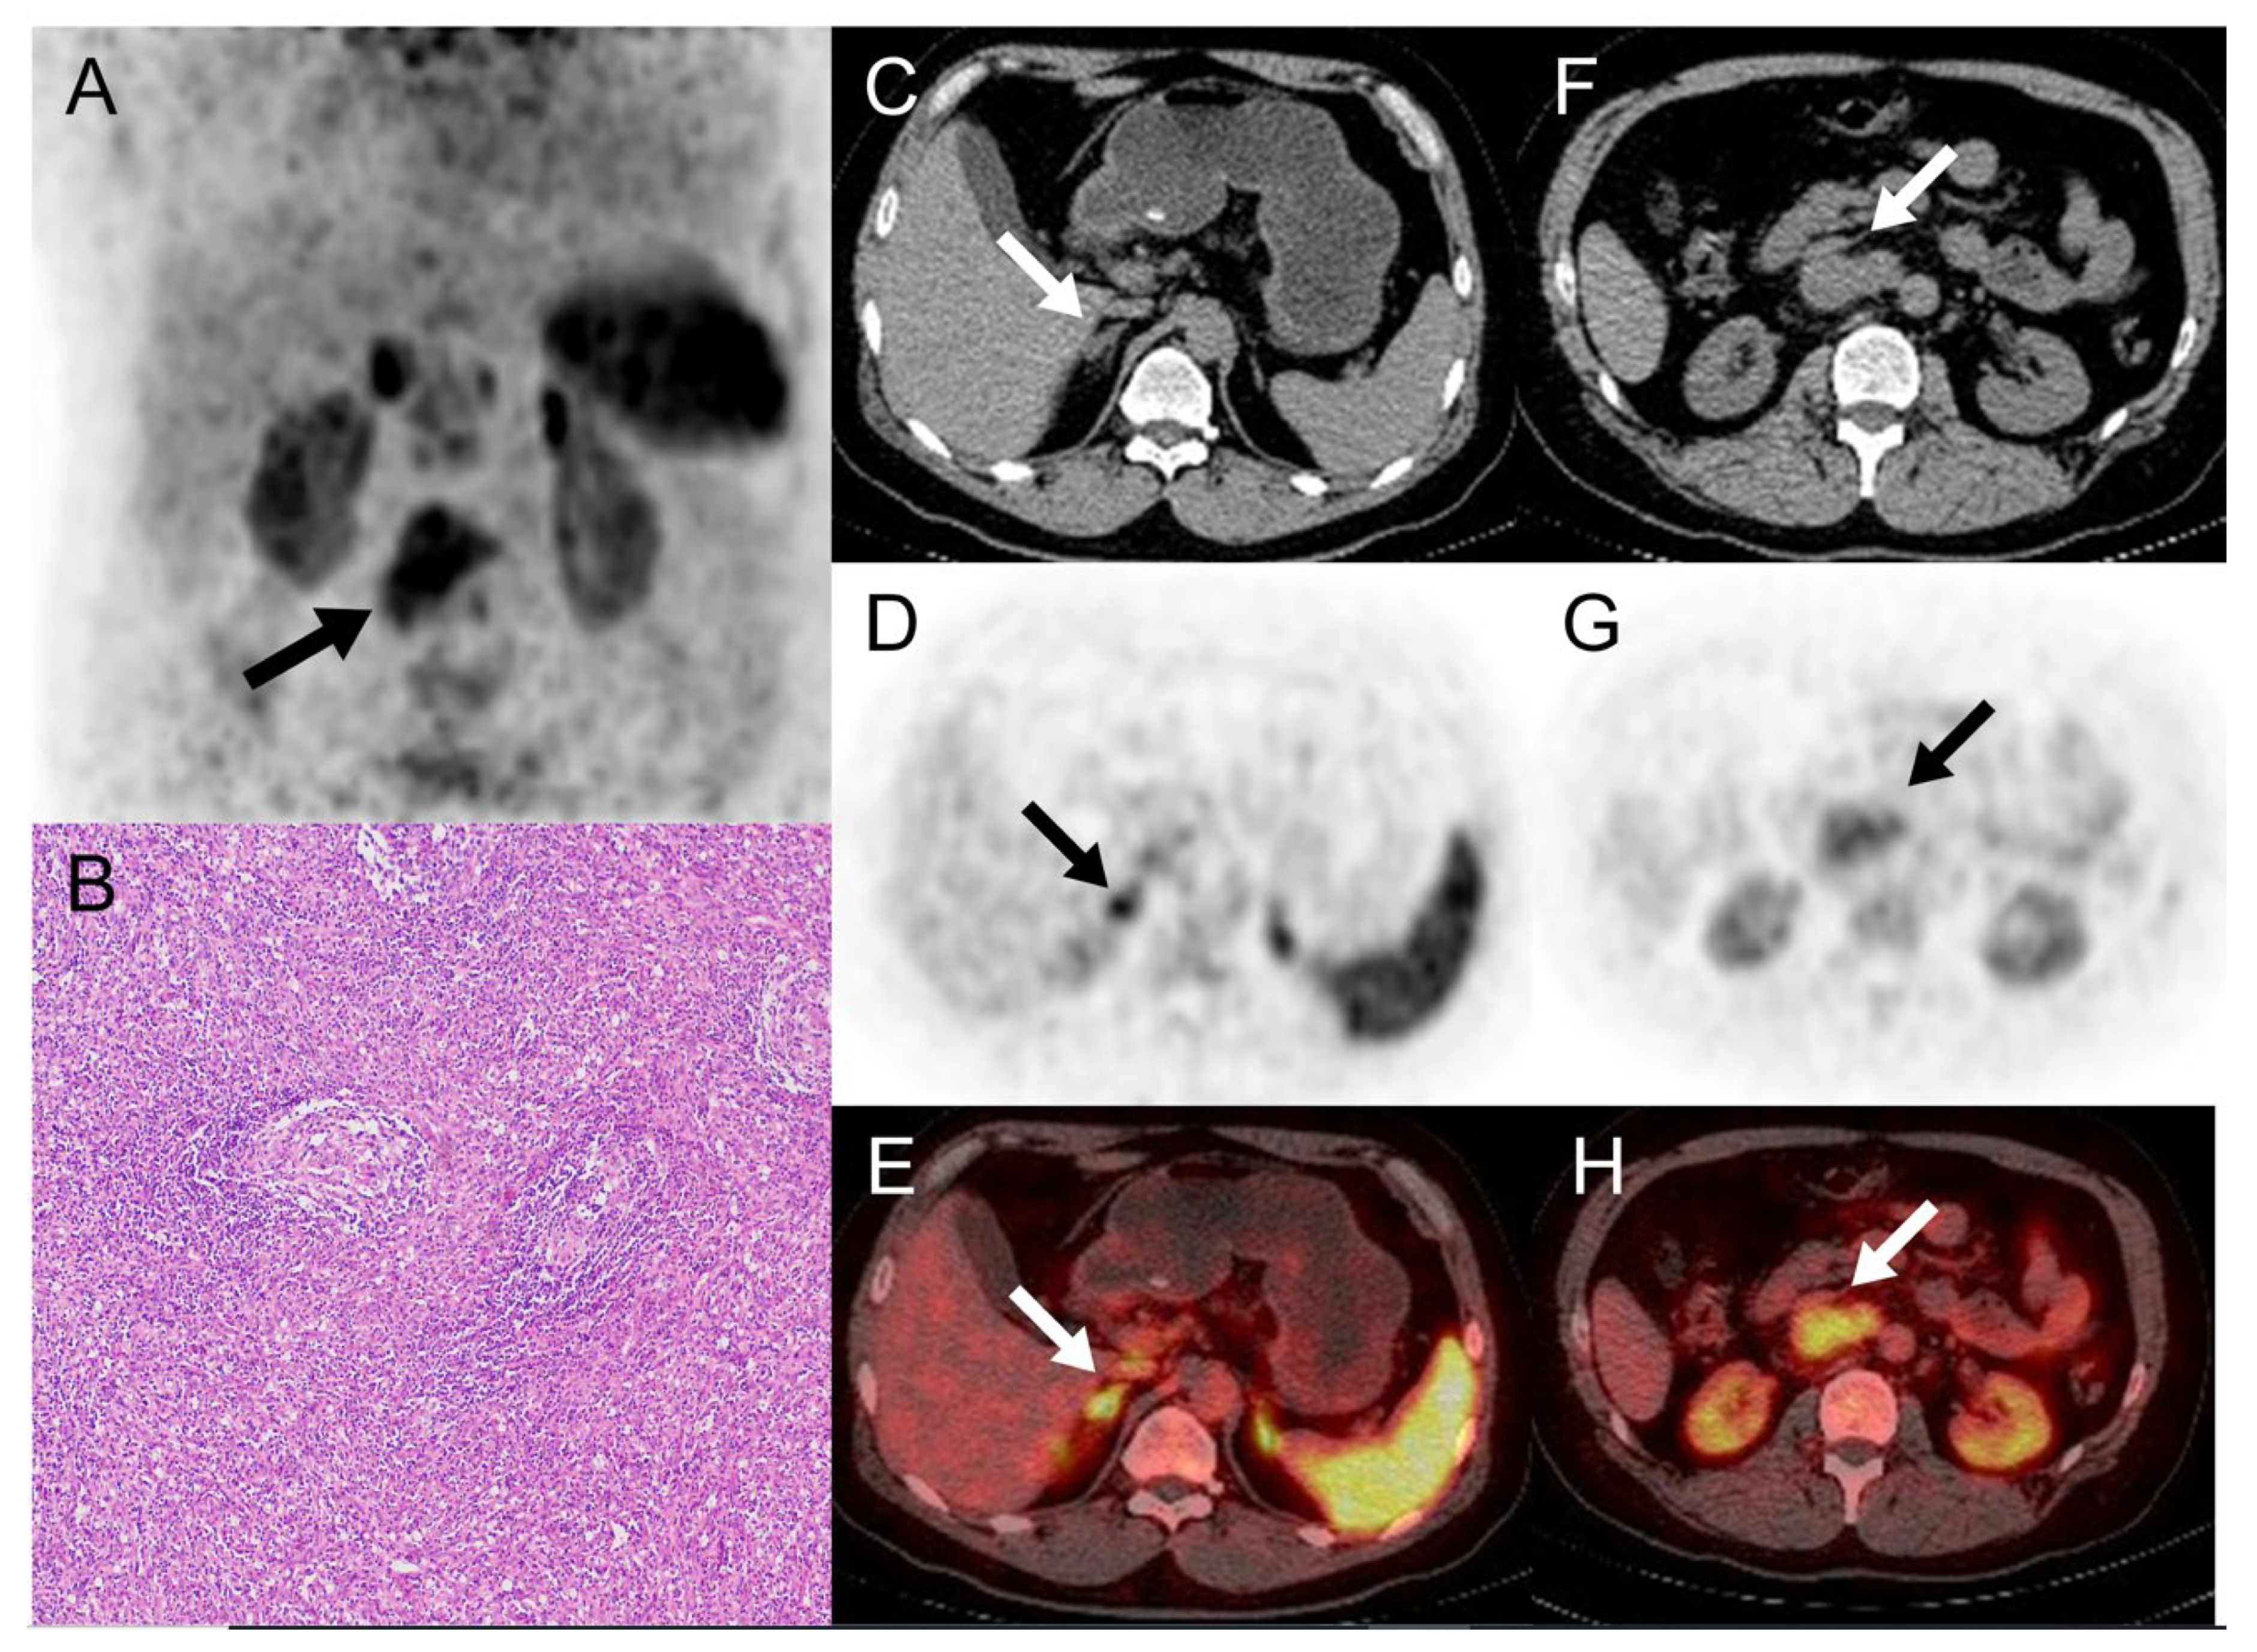

68Ga-DOTATATE and 68Ga-Pentixafor PET/CT in a Patient with Castleman Disease of the Retroperitoneum

Zuo, R.; Xu, L.; Pang, H. 68Ga-DOTATATE and 68Ga-Pentixafor PET/CT in a Patient with Castleman Disease of the Retroperitoneum. Diagnostics 2024, 14, 372. https://doi.org/10.3390/diagnostics14040372